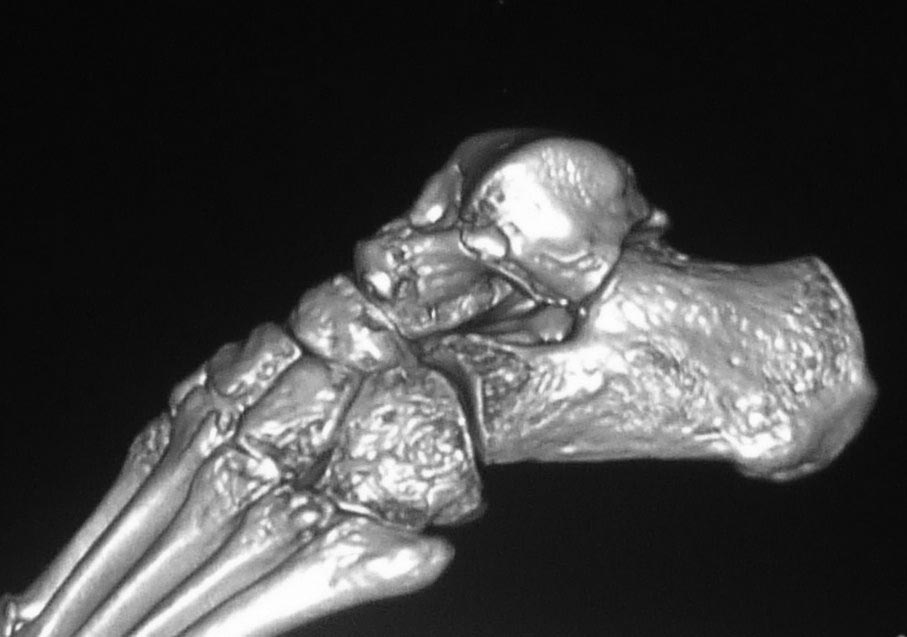

Во вложении похожий случай, оперированный 10 дней назад (с послеоперационными снимками). Для сравнения стрелками на двух рентгенограммах показан нависающий над пяточной костью вывихнутый фрагмент таранной кости. На компьютерной томограмме видно гораздо лучше. Так что о живом подтаранном суставе при сохраняющемся подвывихе говорить не приходится. Кстати, остеотомия внутренней лодыжки в такой ситуации - нормальный этап доступа, который должен планироваться до операции, а не быть следствием "тяжелой репозиции". Сейчас же, судя по плотности проксимального фрагмента, нужно исключать асептический некроз таранной кости и ее несращение. От этого будет зависеть тактика. Без КТ не обойтись. Во всяком случае, артродез голеностопного сустава при несросшейся разрушающейся таранной кости точно не будет правильным решением.